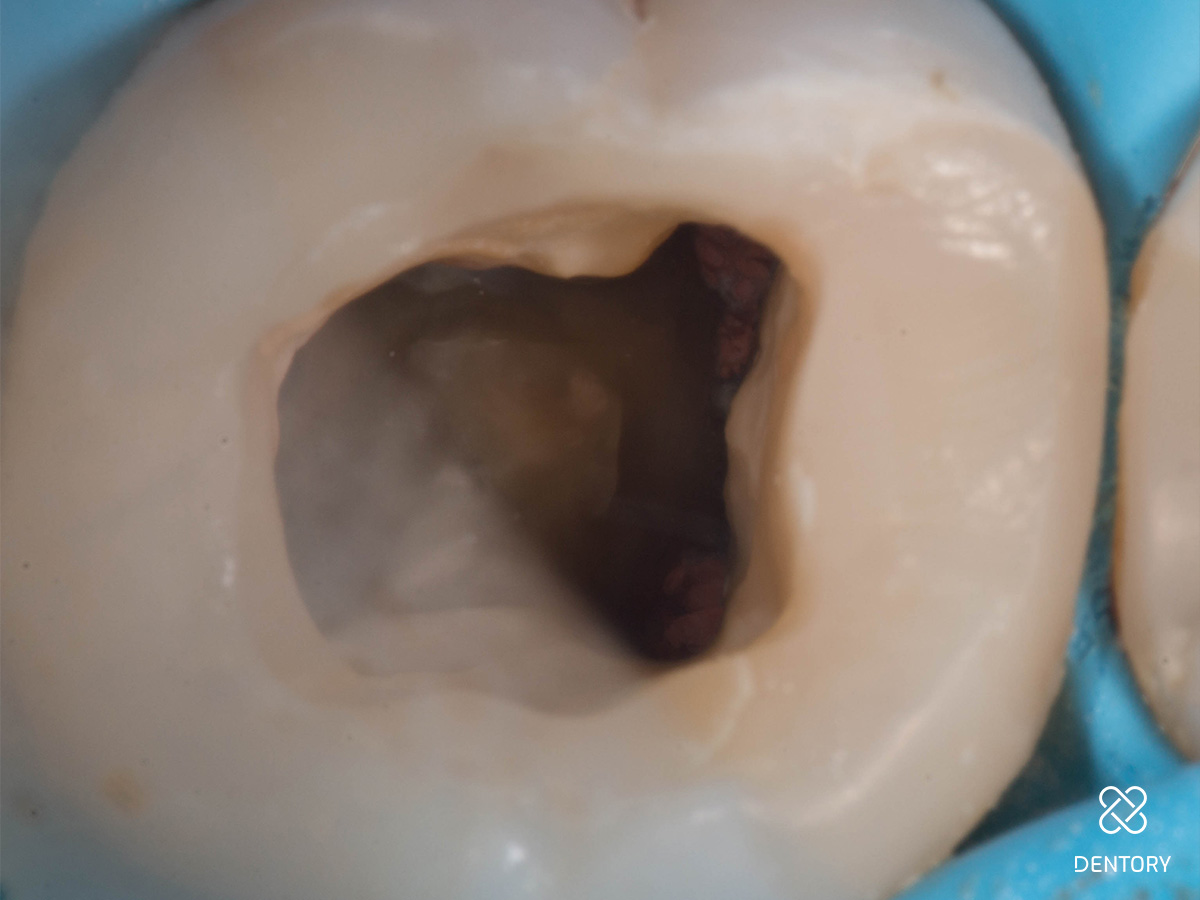

Abbildung 7

Zweite Sitzung: Zentral ist der temporäre Verschluss im Prä-Endo-Aufbau sichtbar.

Abbildung 8

DVT-Ausschnitte nach Entfernung der alten Guttapercha.